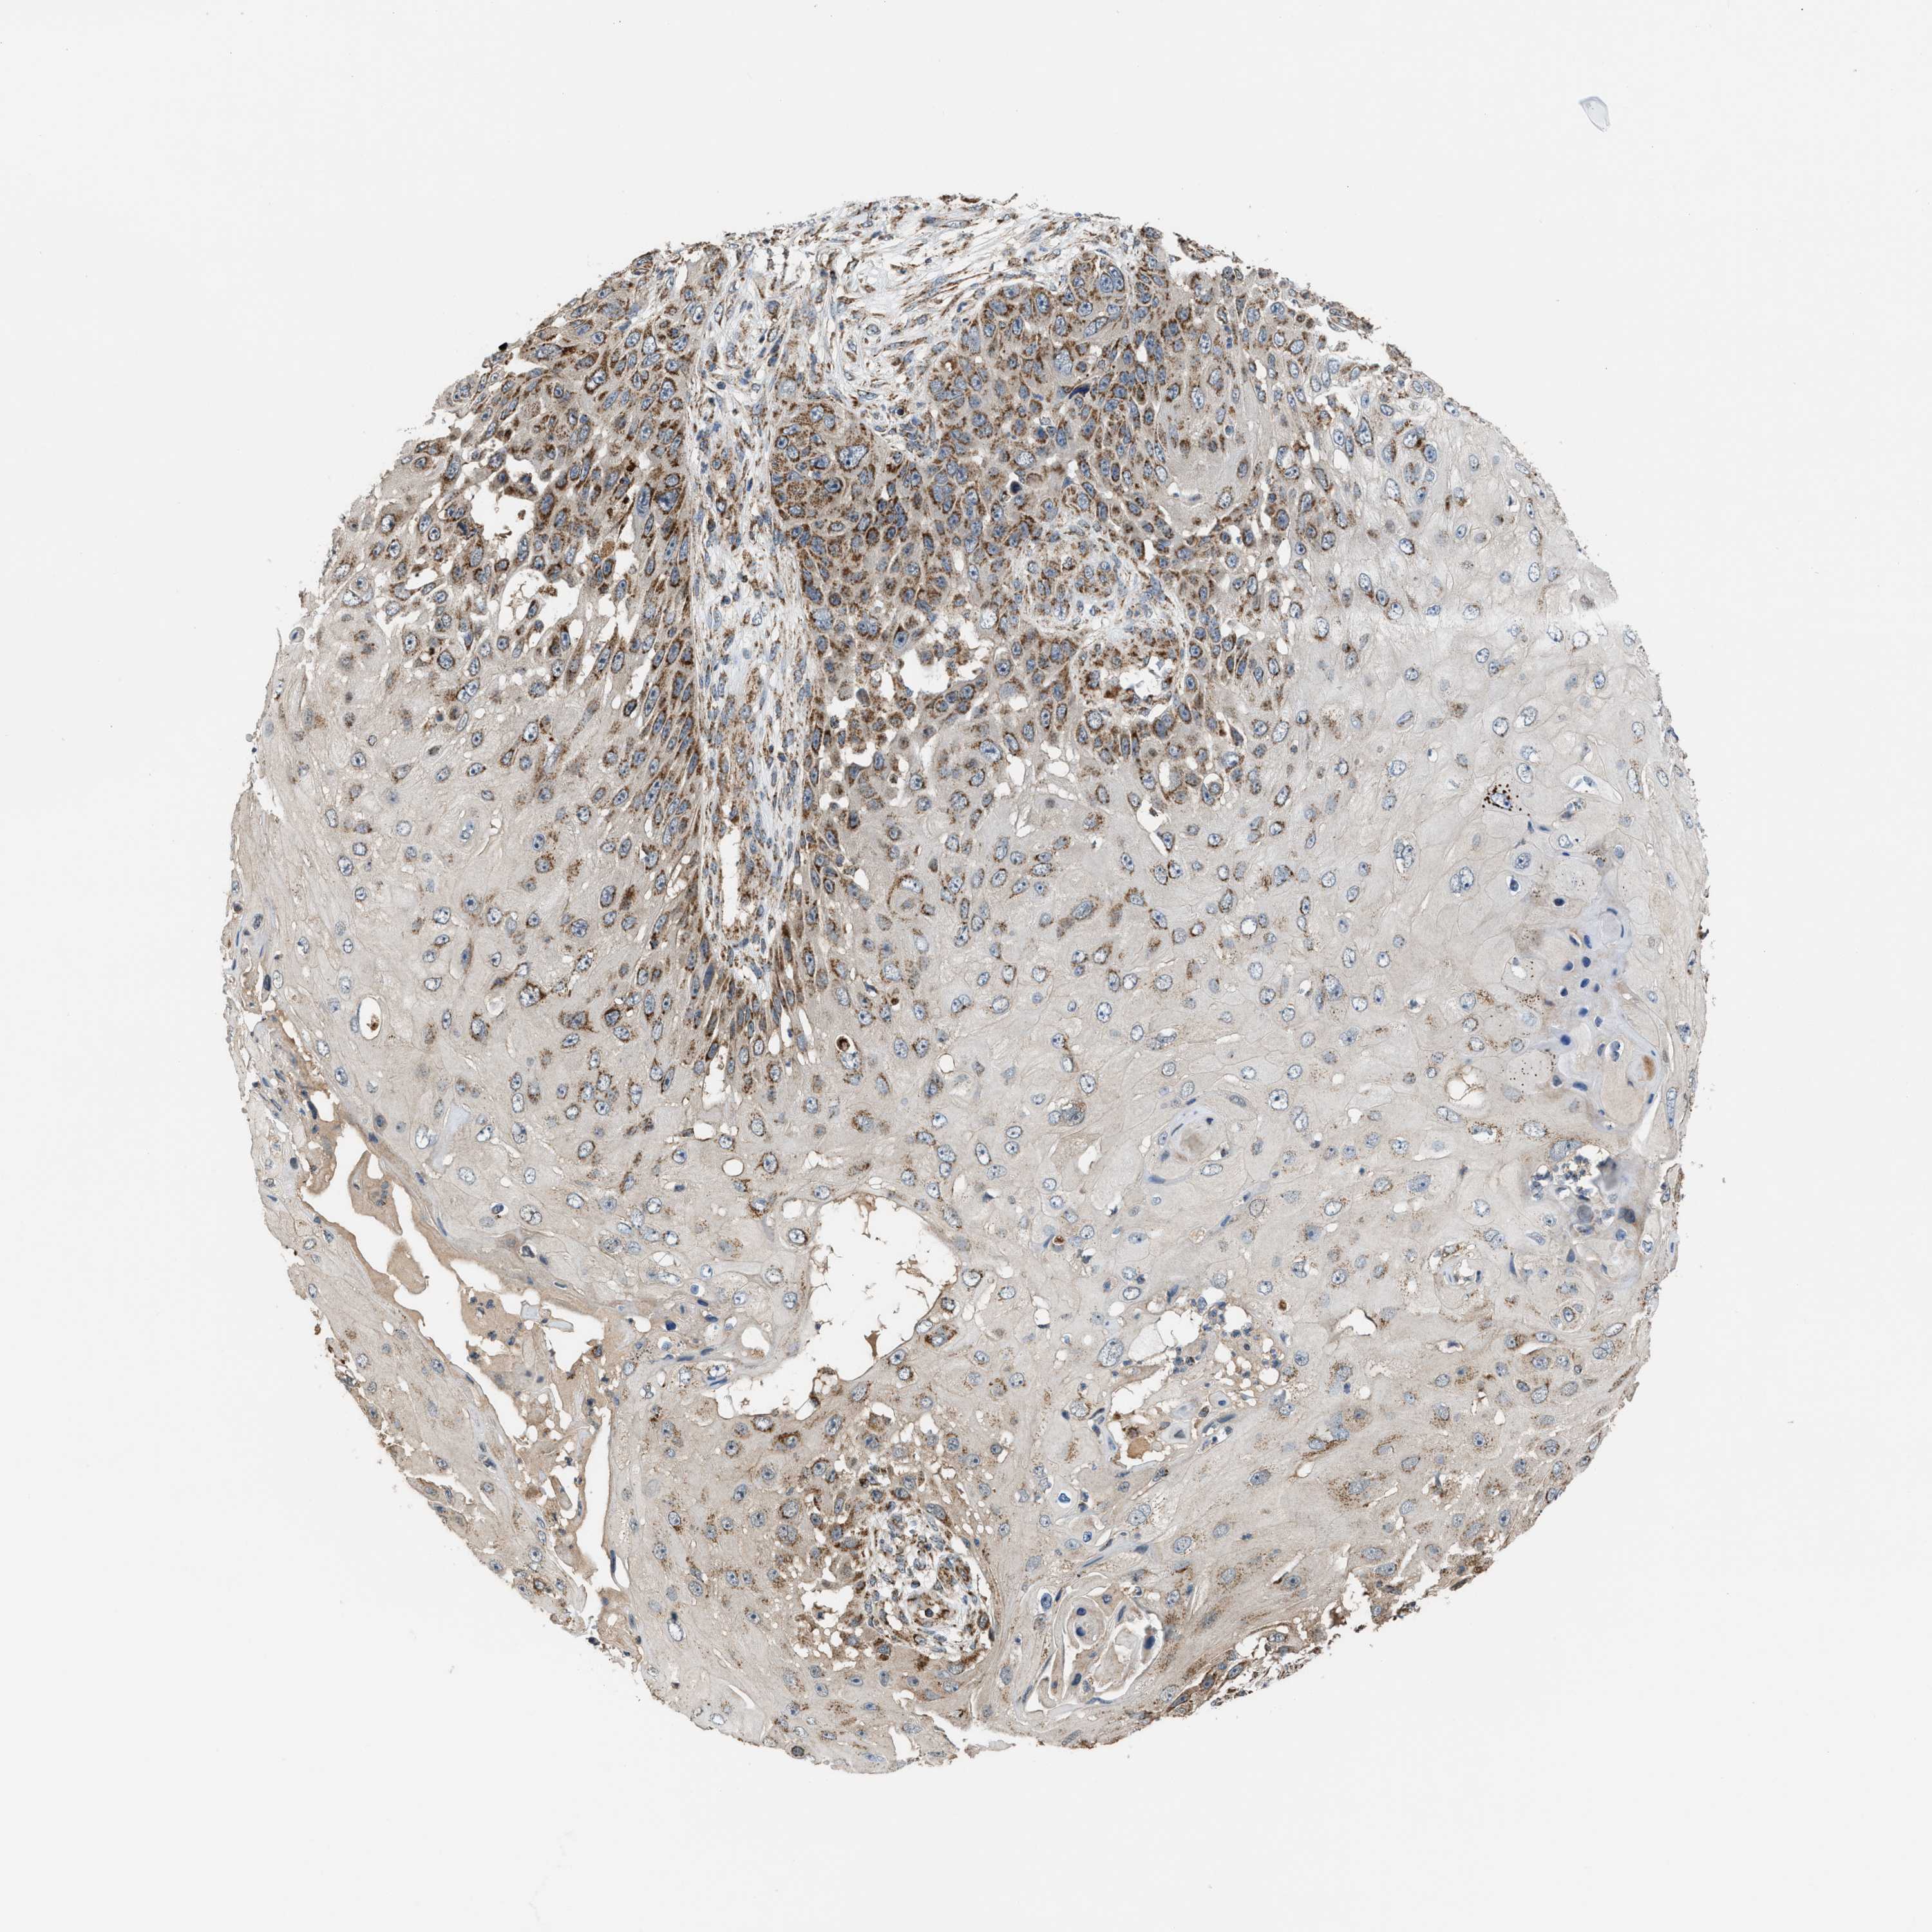

CANCER SKIN CANCER Show tissue menu

SKIN CANCER - Protein expressioni

A mouse-over function shows sample information and annotation data. Click on an image to view it in a full screen mode. Samples can be filtered based on level of antibody staining by selecting one or several of the following categories: high, medium, low and not detected. The assay and annotation is described here.

Each image is clickable and will lead to virtual microscopy that enables deeper exploration of all samples and also displays staining intensity scores, fraction scores and subcellular localization as well as patient and tissue information for each sample.

Antibody HPA021641

Squamous cell carcinoma, NOS

Squamous cell carcinoma, metastatic, NOS

Basal cell carcinoma

Adnexal tumor, benign